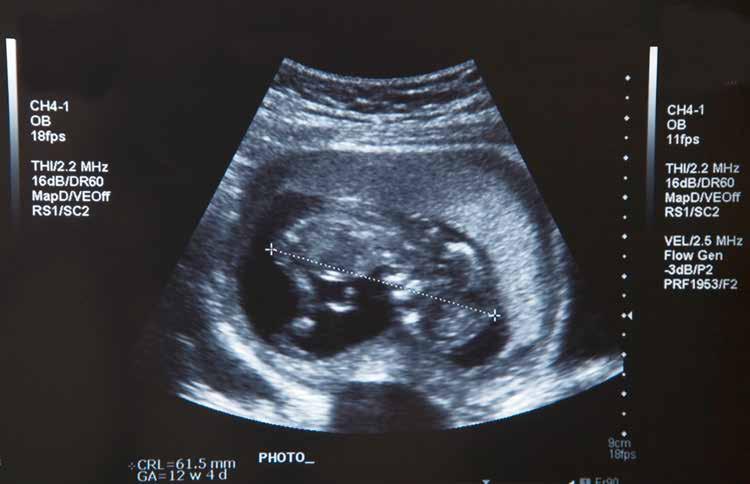

Ultrasound/Sonograms: An essential part of Prenatal Care

For many Moms-to-be, a first ultrasound is a life-changing experience. As a medical procedure, it is one that patients look forward to.

A fetal ultrasound or sonogram is an imaging technique that uses high-frequency sound waves to produce images of a baby in the uterus. An ultrasound can help your doctor evaluate your baby’s growth and development as well as gauge the progress of your pregnancy.

Your first ultrasound will typically be done between 18 and 20 weeks, but you may have one before 12 weeks to confirm your due date. You may also have an earlier ultrasound — or more than one — if yours is a high-risk pregnancy, if you have any pain or bleeding, if you have a history of having children with birth defects, or if another prenatal test or exam shows something abnormal. In addition, you’ll have additional ultrasounds if you have a chronic illness such as diabetes or a history of ovarian cysts or fibroids.

A first trimester ultrasound exam is done to evaluate the presence, size, and location of your pregnancy. It also helps your doctor to evaluate any problems, screen for abnormalities, or confirm a diagnosis. If your baby’s health needs to be monitored more closely, additional ultrasounds will be recommended.

What happens during an ultrasound? After you lay down on the

exam table, a small amount of gel is applied to the skin of your abdomen. A device called a transducer is applied to your skin, sending high-frequency sound waves into your body that reflect off the internal structures. The echoes are received by the transducer and turned into a picture on the screen.

All fetuses are approximately the same size in the early weeks of pregnancy, so a sonogram allows your doctor to approximate your due date. If you have your sonogram between 7 and 13 weeks, your doctor can set your due date within about 3 days!

A mid-pregnancy ultrasound is done at around 20 weeks. This sonogram is also called the anatomy scan. Your doctor will listen to the baby’s heartbeat, check for physical abnormalities, check the organs, determine if there’s more than one baby (twins!), measure the amount of amniotic fluid, check the location of the placenta, and measure your baby to be sure he or she is the right size for his or her gestational age. And yes – determine the sex of your baby… This is the exam where you can catch a glimpse of your baby – and go home with a picture or two!

When properly done, an abdominal ultrasound poses no risk to you or your baby. In fact, there are many benefits to checking on your baby’s development during pregnancy. It is generally advised that an ultrasound be performed only if medically indicated.